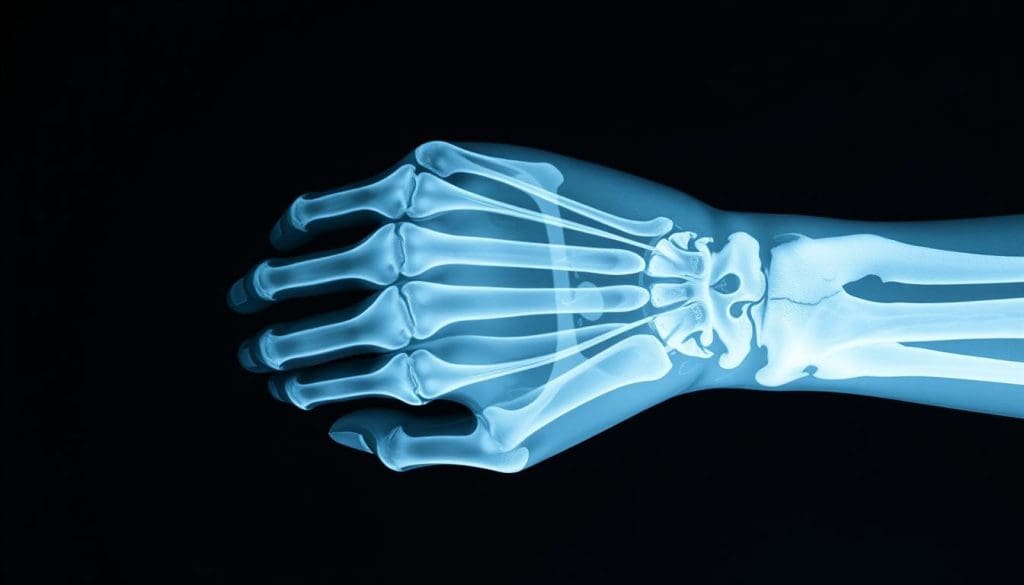

Understanding X-Ray Technology for Fracture Detection

X-ray technology is key in diagnosing bone fractures. It uses electromagnetic waves to show the body’s inside, focusing on bones.

How X-Rays Work to Visualize Bone Structures

X-rays send radiation through the body. Denser materials like bone absorb more, showing up white. Softer tissues let more X-rays through, appearing gray or black. This helps doctors spot fractures and bone issues.

Strengths of X-Ray Imaging in Fracture Diagnosis

X-ray imaging is quick and widely available, perfect for emergencies. It clearly shows bone structures, helping find most fractures. Plus, it’s cheaper than other imaging like MRI.

Limitations and Blind Spots of X-Ray Technology